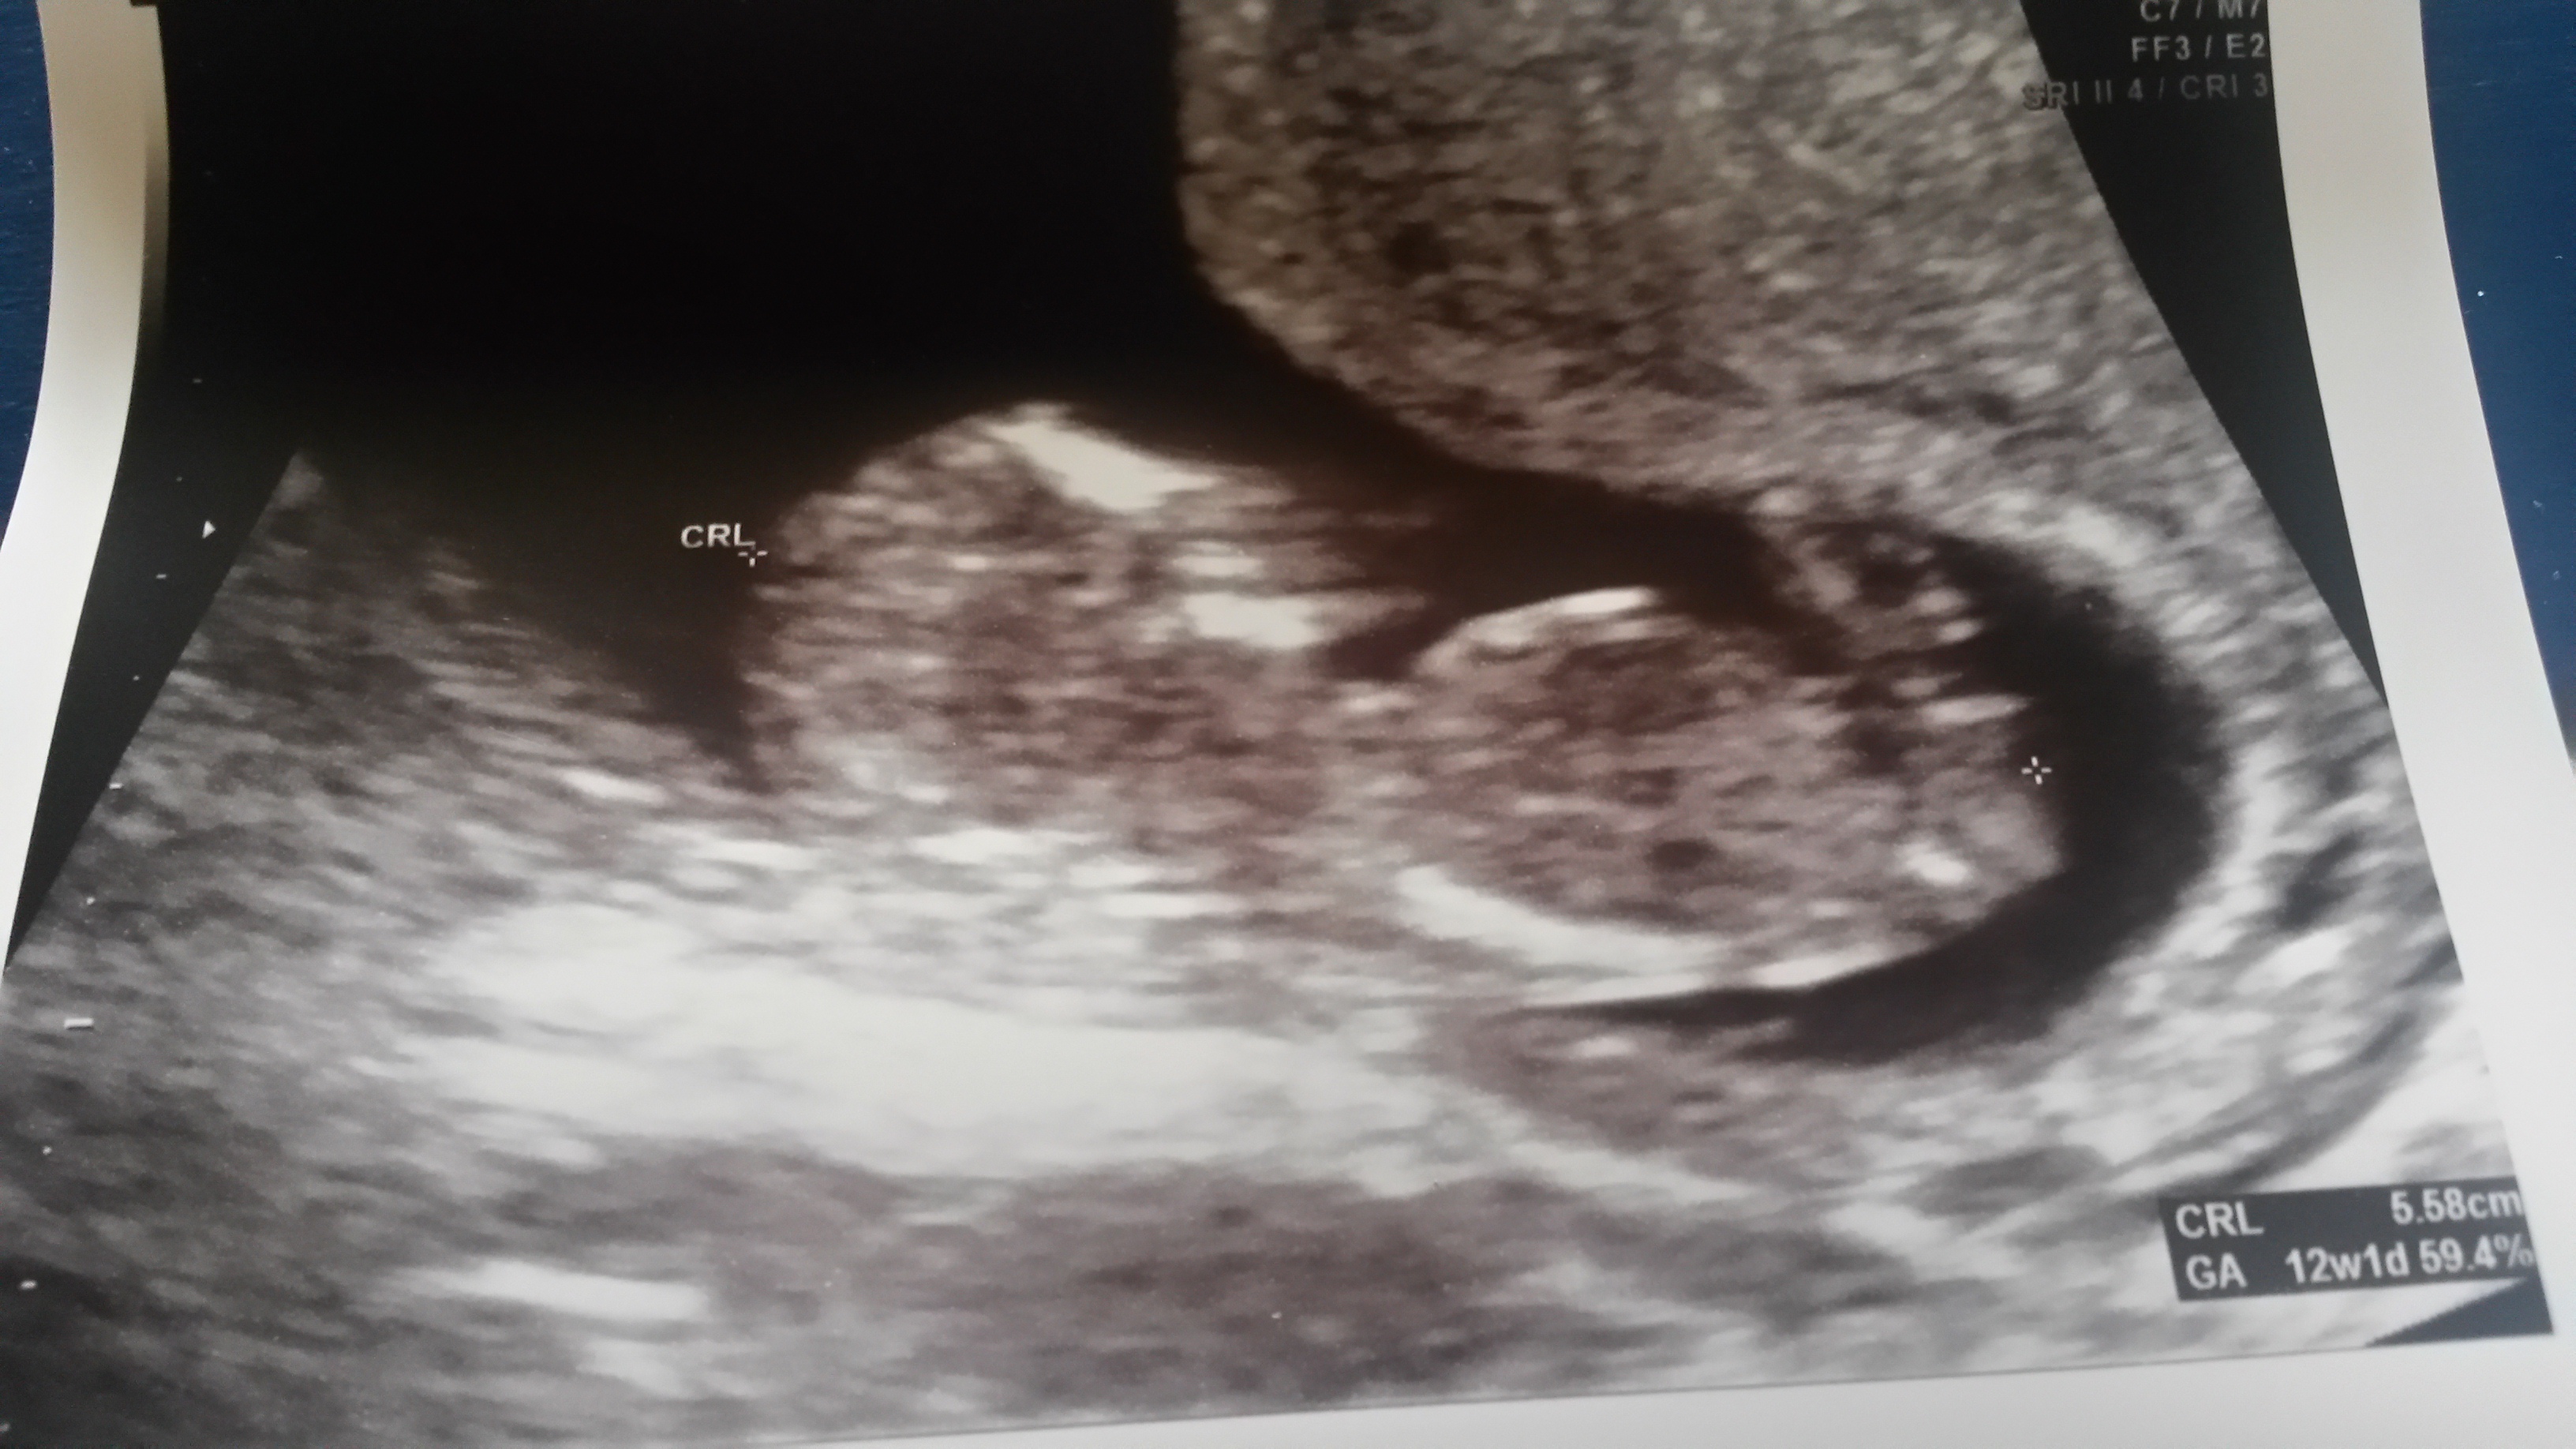

Any guesses? 12 w 4 days